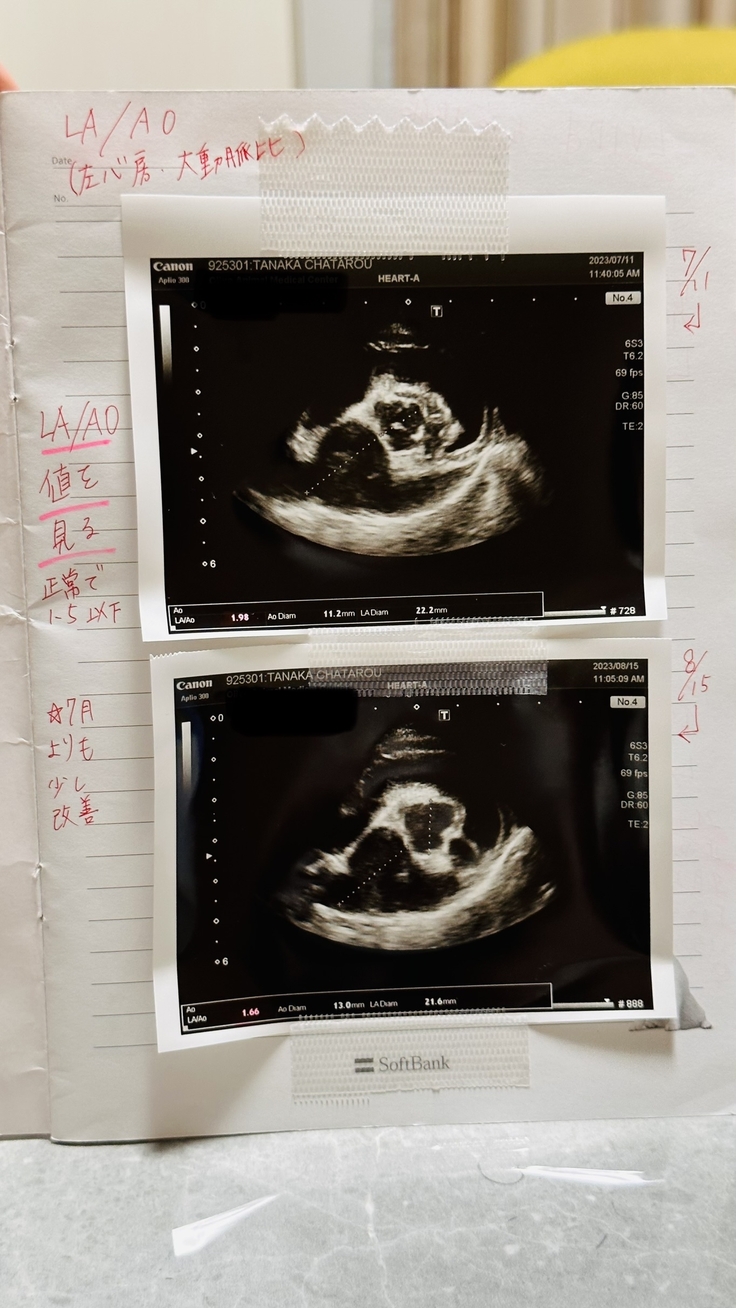

LA/AO(左心房/大動脈比)*正常値1.5以下

こちらも前回より数値が改善されており◎

前回7月→1.98

今回8月→1.66